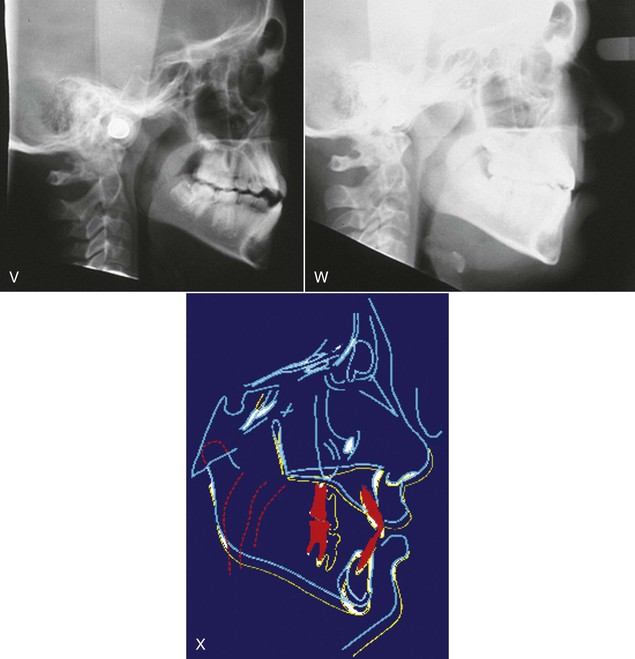

Keles et al.34 studied the effects of varying the force direction on maxillary orthopedic protraction in two groups of patients. The first group received protraction headgear with a force applied by intraoral elastics and the second group received a force applied with a modified protraction headgear as described above.9 The authors reported that in the first group the maxilla rotated counterclockwise (Fig. 16-10), resulting in downward and backward rotation of the mandible, while in the second group an anterior translation of the maxilla with no to minimal mandibular rotation occurred. This important study showed that predictable changes can be achieved in the direction of maxillary advancement with desired or without undesirable mandibular changes.

Figure 16-10 Force diagram of a protraction headgear device using intraoral elastics to deliver force. Note the clockwise moment on the midface and dentition resulting in a downward and backward rotation of the mandible.